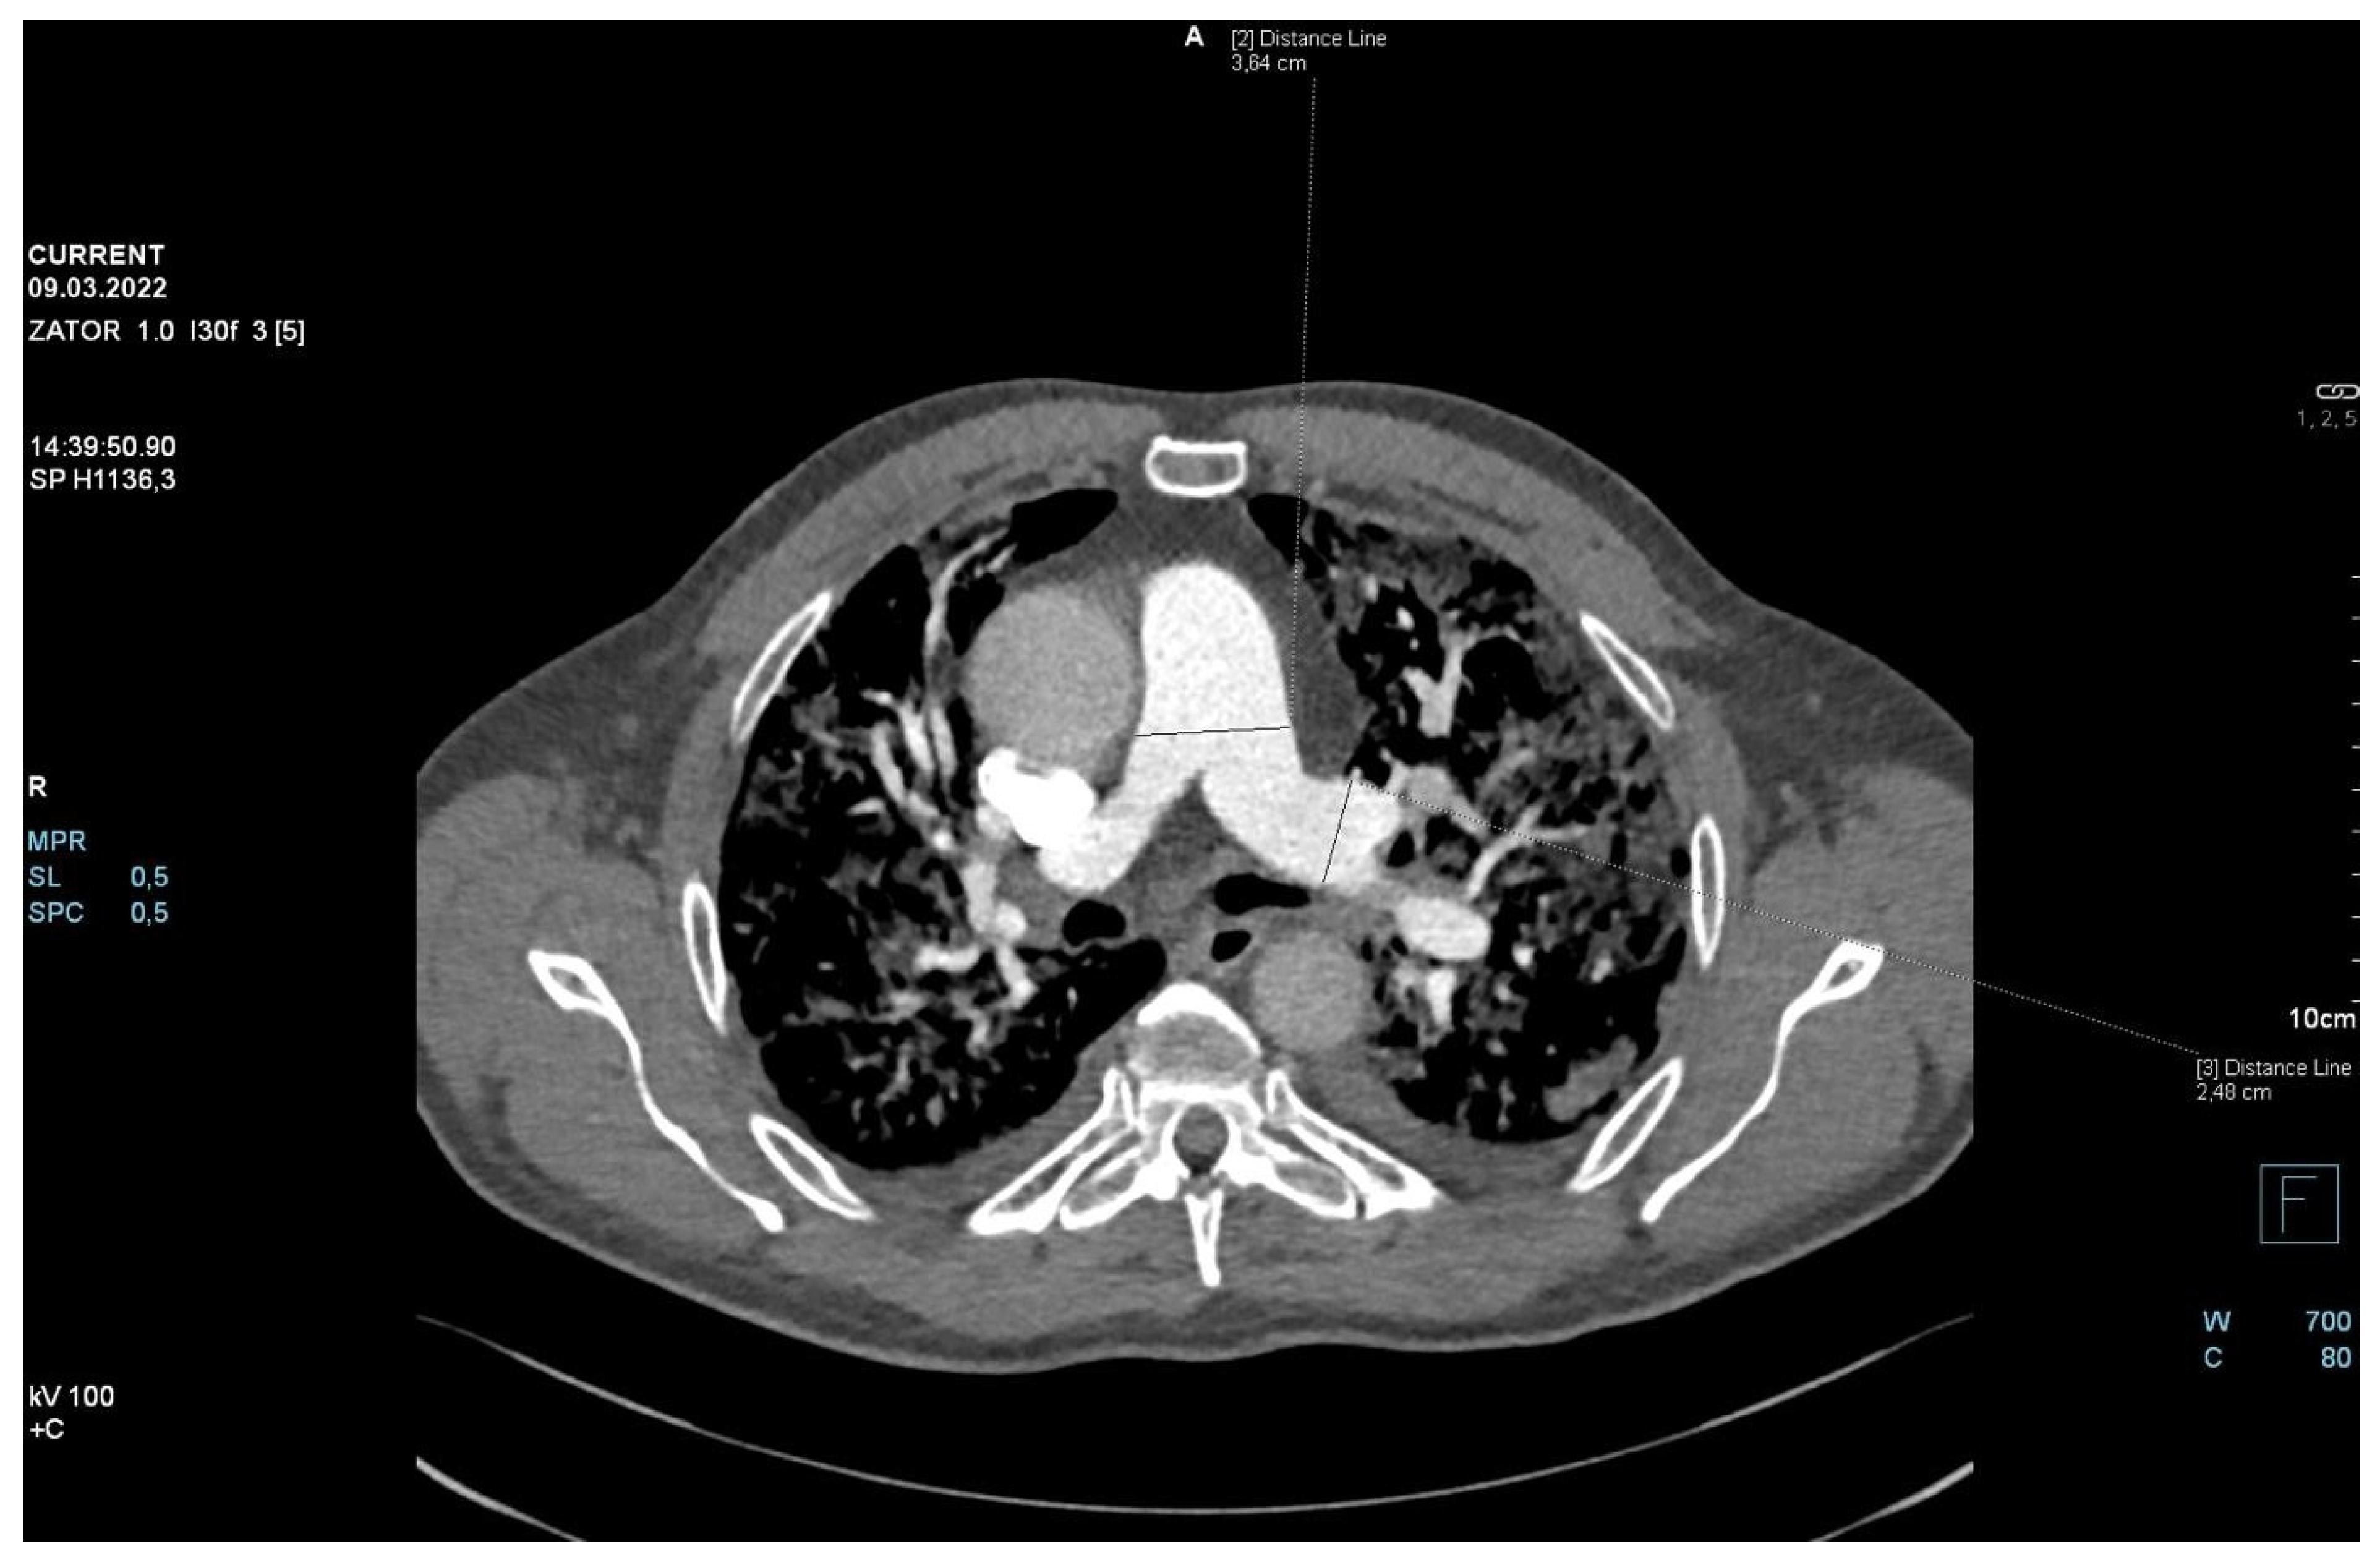

The patient required oxygen therapy, and initially, due to a lack of diagnosis, he received empirically broad-spectrum antibiotics (meropenem, linezolide). On laboratory testing, a further increase in inflammatory and coagulation biomarkers (CRP, ferritin, interleukin-6, D-Dimer, fibrinogen) was observed. Blood cultures as well as a respiratory PCR multitest were negative. Due to the dynamic increase in D-dimers and the elevation of cardiac biomarkers (BNP, NT-proBNP) along with dyspnea, an angio-CT was performed. It excluded pulmonary embolism, but it revealed widening of the pulmonary trunk and pulmonary arteries, as well as alveolar compaction in both lungs and bilateral pleural effusion. Pulmonary edema was diagnosed (Figure 2, Figure 3 and Figure 4).

Figure 2.

Angio-CT scan.

Figure 3.

Figure 4.